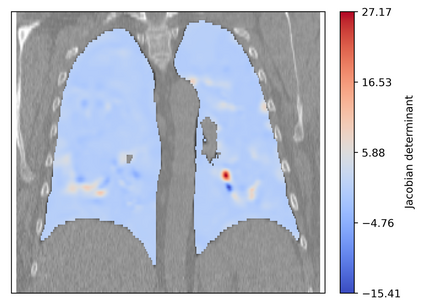

Deformable image registration is a fundamental task in medical image analysis and plays a crucial role in a wide range of clinical applications. Recently, deep learning-based approaches have been widely studied for deformable medical image registration and achieved promising results. However, existing deep learning image registration techniques do not theoretically guarantee topology-preserving transformations. This is a key property to preserve anatomical structures and achieve plausible transformations that can be used in real clinical settings. We propose a novel framework for deformable image registration. Firstly, we introduce a novel regulariser based on conformal-invariant properties in a nonlinear elasticity setting. Our regulariser enforces the deformation field to be smooth, invertible and orientation-preserving. More importantly, we strictly guarantee topology preservation yielding to a clinical meaningful registration. Secondly, we boost the performance of our regulariser through coordinate MLPs, where one can view the to-be-registered images as continuously differentiable entities. We demonstrate, through numerical and visual experiments, that our framework is able to outperform current techniques for image registration.